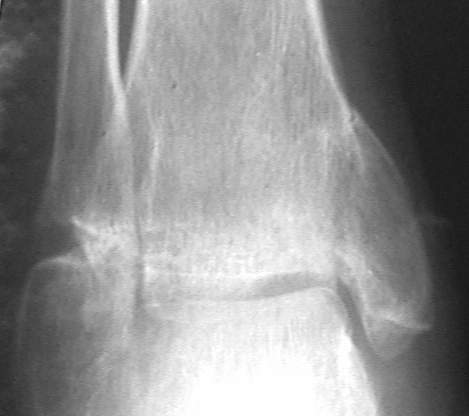

У больного травма в августе 2001 г. Лечился консервативно, Проводилась иммобилизация гипсовой лонгетой 3 мес. В последующем местное лечение. Остается контрактура боли в области наружной лодыжки. Направлен в наше отделение в конце января 2002 г Планируется костная аутопластика, остеосинтез пластиной, винтами перелома наружной лодыжки. Решается вопрос о коррекции неправильно сросшегося перелома внутренней лодыжки. Рентгенограммы: фас; профиль; план Сергей Зырянов

Кто сказал, что это ложный сустав (какой?) лодыжки?

Перелом сросся, другое дело что с небольшим смещением - с варизацией - это естественно при смещении внутренней лодыжки кверху.

Однако в чем проблема и что даст операция?

Надо сделать компьютерную томография и объектизировать истинное состояние переломов лодыжек. Пока не видно подвывиха таранной кости, а ложный сустав внутренней лодыжки (я его не вижу)в основном не вызывает функциональных растройств в голеностопном суставе.